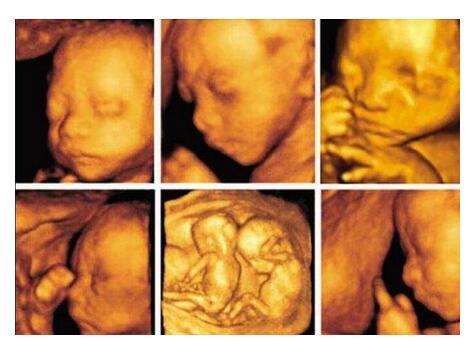

爱上海 现在的彩超以四维彩超为主,三维彩超和四维彩超的区别主要在于在一个“时间维”,也就是说,三维彩超是图片,是静态的,四维彩超是录像,是动态的,可以让孕妈妈看到胎儿一连串的动作,所以四维看起来会更清楚明了,三维彩超只能是某个时间点上的照片,四维彩超的就可以做成DV那样连续的,可以刻录光盘。三维彩超和高清四维彩超一样的有排畸的作用,高清四维彩超更加精确。三维彩超侧重观察五脏六腑是否畸形,排除结构畸形。四维彩超还观察运动神经系统是否正常,运动是否协调。

三维彩超、四维彩超的图像则是后期生成的,并不是说观察到的图像就是三维、四维的,而是仍然用普通彩超观察,然后通过仪器中的转换软件将观察到的平面图像转成三维、四维的立体图像,说得更直白一点,如果将你的家用电脑中装上类似软件,你就可以把普通B超的图像自己在家里转换成立体的了。

在诊断的意义上,三维彩超、四维彩超没有任何对诊断更有利的地方,只不过是不懂得B超图像的人也能看出模样而已。它们的意义也就在于,您能看见宝宝还在肚子里的模样了。

爱上海 四维彩超可立体显示胎儿的颜色、面、各器官的发育情况,甚至胎儿在母体里的状态也可以观察到;对胎儿畸形,如唇裂、腭裂、骨骼发育异常、心血管畸形等能早期诊断。了解胎儿宫内动态的一个胎动过程,再者动态摄录胎儿宫内资态,可以让孕妈妈看到胎儿一连串的动作,所以四维看起来会更清楚明了,还可以留作永久的纪念。三维彩超只能是某个时间点上的照片,四维彩超的就可以做成DV那样连续的,可以刻录光盘。而且四维彩超不存在射线、光波和电磁波等方面的辐射,对人体的健康没有任何影响,现今医学上并没有对人体的健康有任何影响的报道。